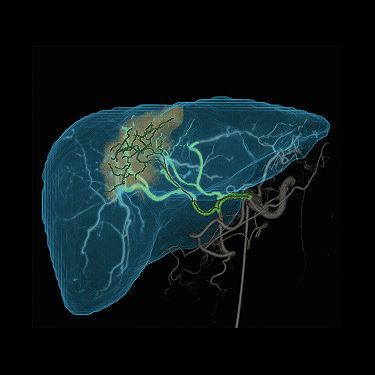

LiverAssistVP11x

Liver ASSIST Virtual Parenchyma

Liver ASSIST Virtual Parenchyma¹ ist eine 3D-Visualisierungssoftwarelösung, die entwickelt wurde, um KI-gestützte virtuelle Parenchymographie bereitzustellen.